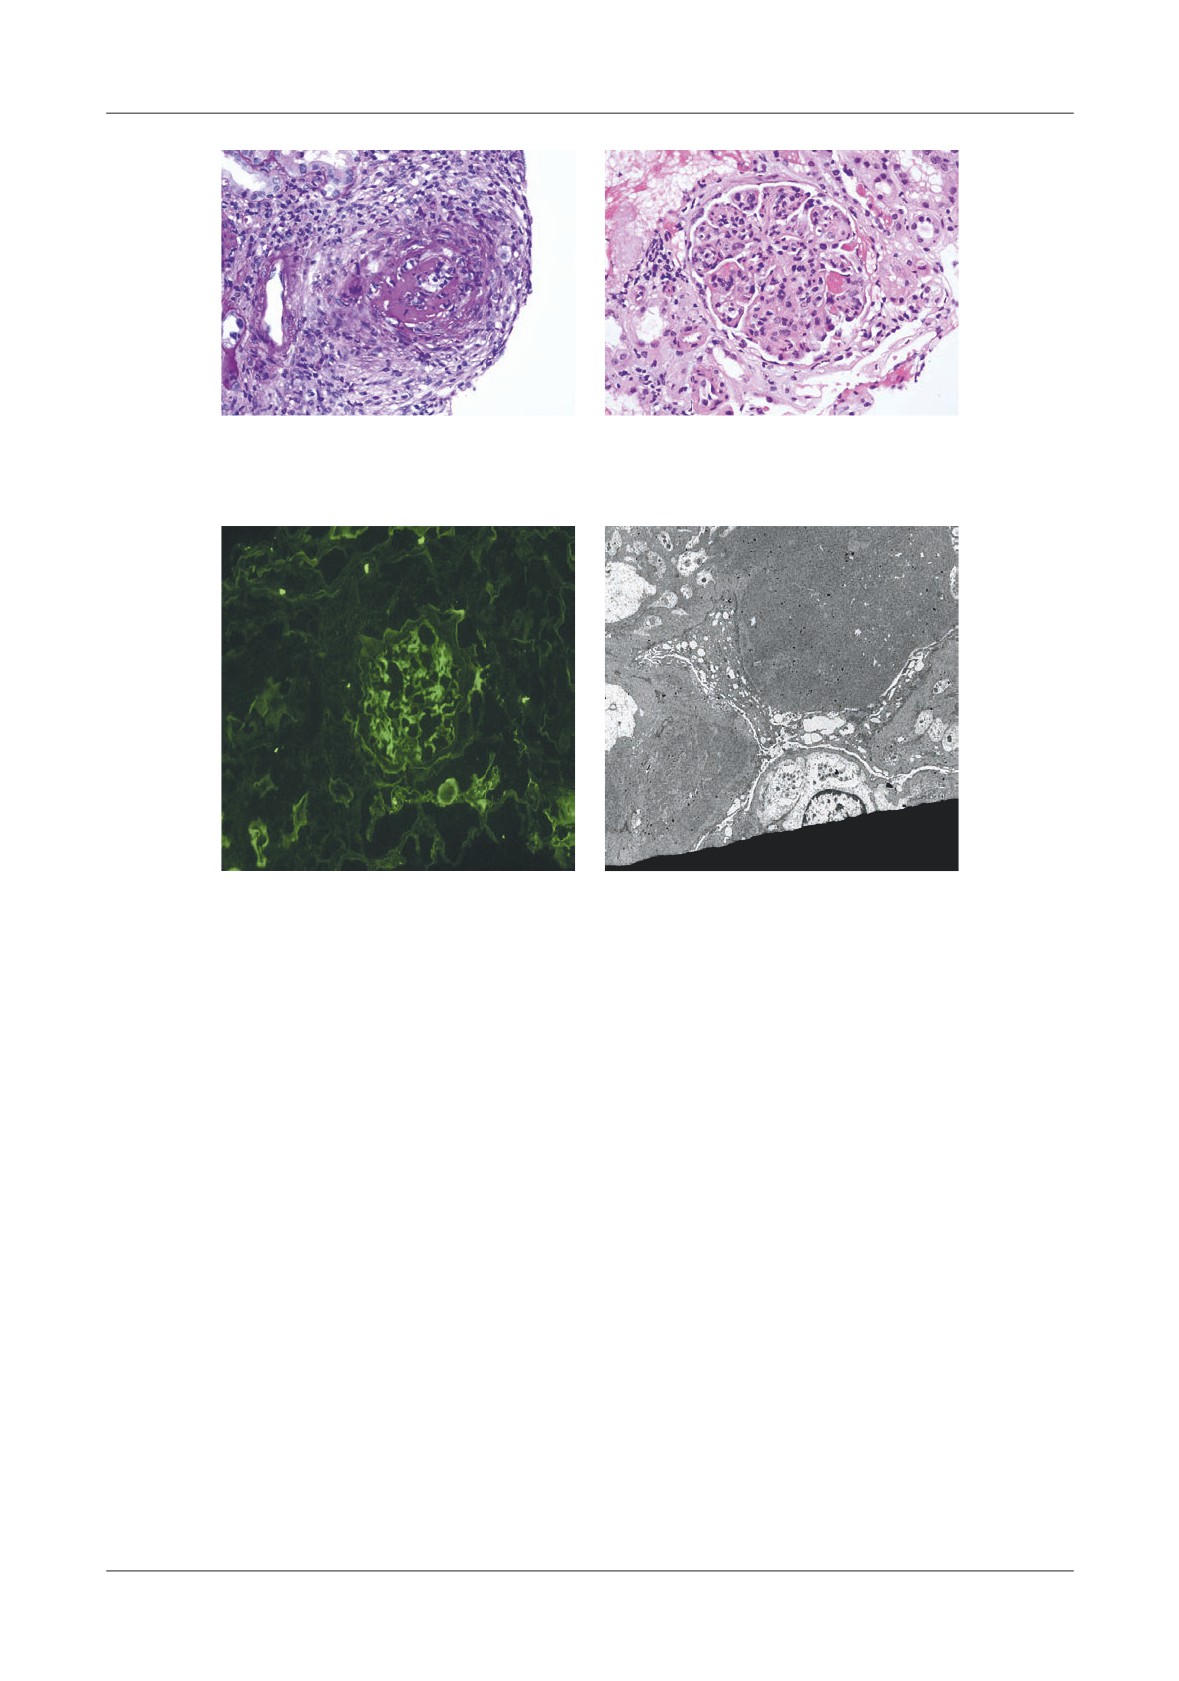

Figure 1. Pancreatic necrosis with the development of a pseudocyst, ileus and colonic in ltration in a 38

-year-old man. A-At admission the CT- shows enlarged pancreas and peripancreatic in ammation,  uid

(N=necrosis, P=pancreas, S=stomach), B-Lique ed necrosis nine days later with partially encapsulated

uid collection in the lesser sac, C-Dilated small bowel loops, with a haustral transverse colon. S=small

bowel, T=transverse colon, D-Five weeks later, fully encapsulated pseudocyst in the lower sac, with

lique ed necrosis in the neck of the pancreas (D=duodenum, N=necrosis, P=pseudocyst, S=stomach)

necrotic tissue (Figure 1).

Figure 4. Pancreatic pseudocyst secondary to necrosis.

A - Liquefaction necrosis in the tail, B - Large pseudocyst bulging into the stomach

Figure 5. Pseudocyst communicating with  the pancreatic duct, A-With CT image of enlarged gland

and peripancreatitis, B-After discharge from hospital, 2 weeks later, CT shows a residual collection,

C-6 months later, the patient had abdominal pain, CT shows an enlarging pseudocyst,

D-Trans gastric punction with  stulography, shows communication with the Wirsung duct